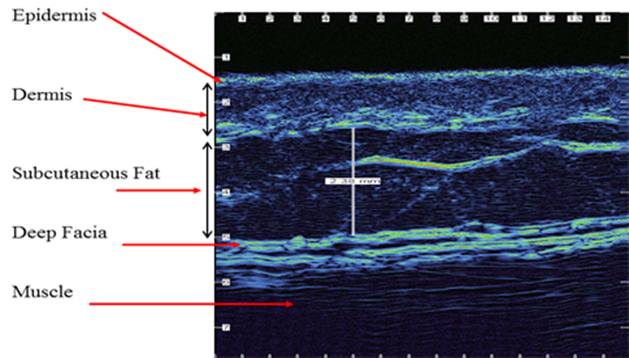

Trả lời: Trước hết chúng tôi rất cảm ơn câu hỏi của bạn, liên quan đến vấn đề siêu âm da để đánh giá gián tiếp hình ảnh và loại thương tổn da và các cơ quan liên quan trong các bệnh lý da hiện nay. Trên thực tế có thể sử dụng nhiều cách siêu âm da, nhân đây chúng tôi xin giới thiệu với bạn về siêu âm da bằng máy UV Scanner. Trên thực tế, rất ít người hiểu chính xác về tình trạng làn da của mình, da không chỉ bảo vệ cơ thể mà còn là tiếng nói cho sức khỏe và là yếu tố tiên quyết tạo nên vẻ đẹp thẩm mỹ. Chúng ta luôn âu lo khi thấy da xuất hiện những dấu hiệu xấu nhưng lại không biết nguyên nhân xuất phát từ đâu. Siêu âm da là cách để bạn giải tỏa những băn khoăn này và xác định được phương pháp chăm sóc điều trị da thích hợp, tiết kiệm thời gian, chi phí, đem lại hiệu quả cao.

Công nghệ siêu âm UV Scaner sử dụng thiết bị đa cảm biến, cùng lúc chẩn đoán về độ ẩm, độ đàn hồi, độ sáng, nhiệt độ của da, kích cỡ lỗ chân lông. Với hiệu ứng 3D, hiển thị hiệu ứng tần số về tình trạng da, cùng chức năng tia tử ngoại giúp đo từng nanomet của lỗ chân lông, nếp nhăn và sự biến đổi sắc tố. Đặc biệt, máy có thể chẩn đoán chính xác da ngay cả khi bạn đã trang điểm. Trong khi các máy thông thường chỉ có thể đo lường trên bề mặt như kiểm soát mụn, vết thâm và khó dự đoán được mức biến đổi da của bạn trong tương lai thì chiếc máy này không chỉ dự đoán được mức lão hóa của da bạn mà còn kiểm soát sâu, toàn bộ tình hình và các bệnh lý về da, từ đó các bác sĩ sẽ cho bạn lời khuyên về chế độ chăm sóc kịp thời và hợp lý nhất.

H1

Siêu âm là các dao động âm thanh, dao động đàn hồi của vật chất. Tác dụng của siêu âm lên cơ thể gây giãn mao mạch làm tăng tuần hoàn tại chỗ, giảm triệu chứng co thắt, tăng dinh dưỡng. Ánh sáng có bản chất vừa là sóng vừa là hạt, khi tác động và cơ thể tạo ra các phản xạ thần kinh gây biến đổi chuyển hoá, tạo ra nhiệt năng, tạo hiện tượng hiệu ứng quang điện, làm hoá gián protein qua đó ảnh hưởng đến quá trình bệnh lý của cơ thể. Gần đây dùng laser để điều trị bệnh da liễu ngày càng được phát triển. Nguyên lý của kỹ thuật này là sự khuếch đại ánh sáng bằng phát xạ cưỡng bức, chùm tia laser khi tác động vào cơ thể tạo ra nhiệt năng, tuỳ mức độ của nhiệt năng gây ra hai tiện tượng: hoại tử đông đặc tế bào (khi nhiệt độ nóng 800C/giây) hoặc gây hiện tượng bốc hơi phá huỷ mạnh (khi nhiệt độ nóng > 1000C khoảng 1/10 giây). Điều trị bằng laser không gây các hiện tượng phá huỷ rộng các tổ chức xung quanh, chùm tia tập trung chiếu vào một diện tích rất nhỏ (có thể tạo được vết cắt tổ chức áp dụng trong phẫu thuật), nên tổn thương chóng lành sau điều trị.

Trên đây là một ví dụ cho thấy siêu âm có thể đơn thuần hoặc phối hợp trong chẩn đoán và điều trị một số bệnh ngoài da có giá trị. Bạn có thể tìm đọc thêm trên các trang mạng với từ khóa google.com/ skin ultrasound